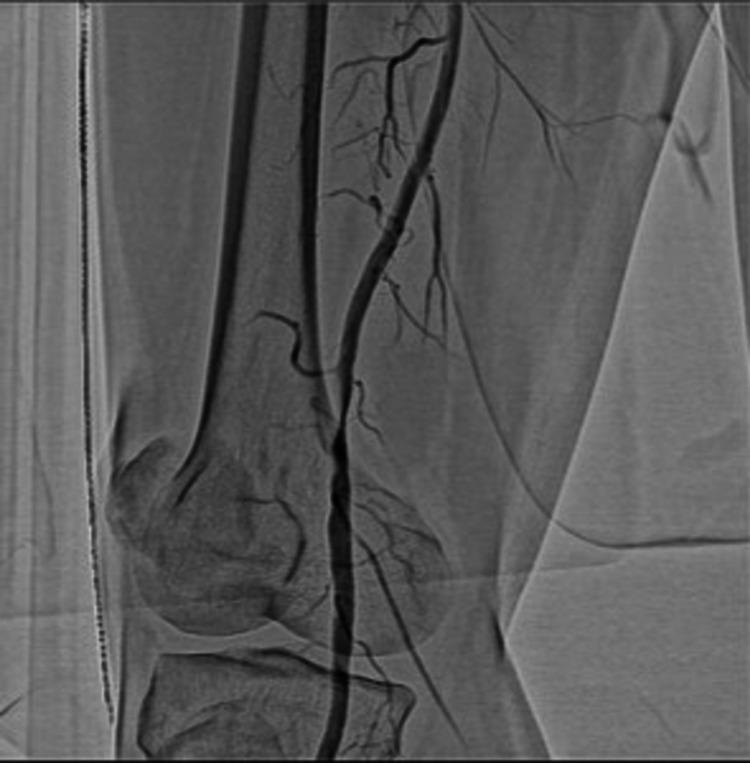

Cystic adventitial disease of the popliteal artery is a rare cause of unilateral intermittent claudication. The etiology of cystic adventitial disease is unknown, and affected patients are younger than those diagnosed with chronic arteriosclerosis. A 62-year-old man presented with a history of right leg claudication, which occurred after walking a distance of 500 m. The patient had no history of cardiovascular risk factors or trauma in the lower extremities. The ankle-brachial pressure index (ABI) was 0.58 in the affected leg. The patient was referred to the cardiovascular department. On Doppler ultrasonography, popliteal artery stenosis was detected. Following an angiogram, drug-coated balloon angioplasty was performed. The claudication improved, as indicated by an ABI of 1.11 in the affected leg. However, following one month of endovascular treatment, claudication had recurred, indicated by an ABI of 0.59. Computed tomography indicated the presence of a stenotic lesion in the popliteal artery, which may have developed from compression on the artery due to the presence of a surrounding periarterial cyst. The patient was subsequently diagnosed with cystic adventitial disease of the popliteal artery and was referred for vascular surgery. During surgery, the popliteal artery was exposed by the posterior approach; the artery showed circumferential enlargement and complete resection of the adventitial layer was performed. The patient had a successful postoperative recovery and the claudication disappeared (ABI of 1.14). Surgical management is an effective curative treatment for cystic adventitial disease of the popliteal artery that shows better efficacy than endovascular treatment. In the future, diagnostic methods for cystic adventitial disease should include computed tomography or magnetic resonance imaging with T1- and T2-weighted images.

腘动脉囊性外膜疾病是单侧间歇性跛行的罕见病因。囊性外膜疾病的病因尚不清楚,且患病患者比被诊断为慢性动脉硬化的患者更年轻。一名62岁男性,有右腿跛行病史,行走500米后出现症状。该患者无心血管危险因素史或下肢外伤史。患侧踝肱压力指数(ABI)为0.58。患者被转诊至心血管科。经多普勒超声检查,发现腘动脉狭窄。血管造影后,进行了药物涂层球囊血管成形术。患侧ABI为1.11,表明跛行症状有所改善。然而,血管内治疗一个月后,跛行复发,ABI为0.59。计算机断层扫描显示腘动脉存在狭窄病变,可能是由于周围动脉周围囊肿对动脉的压迫所致。该患者随后被诊断为腘动脉囊性外膜疾病,并被转诊接受血管手术。手术中,通过后路暴露腘动脉;动脉呈环形增粗,并对外膜层进行了完整切除。患者术后恢复良好,跛行消失(ABI为1.14)。手术治疗是治疗腘动脉囊性外膜疾病的有效治愈方法,其疗效优于血管内治疗。未来,囊性外膜疾病的诊断方法应包括计算机断层扫描或带有T1和T2加权图像的磁共振成像。